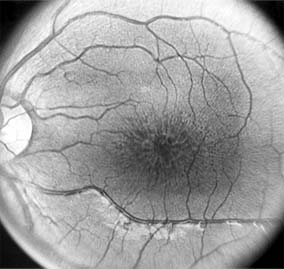

Figure 10-3

Figure 10-3: Fluorescein angiogram of central serous chorioretinopathy shows active disease with both a retinal pigment epithelial detachment (small arrows) and a sensory retinal detachment (large arrows). Two foci of inactive disease (open arrows) are also present.